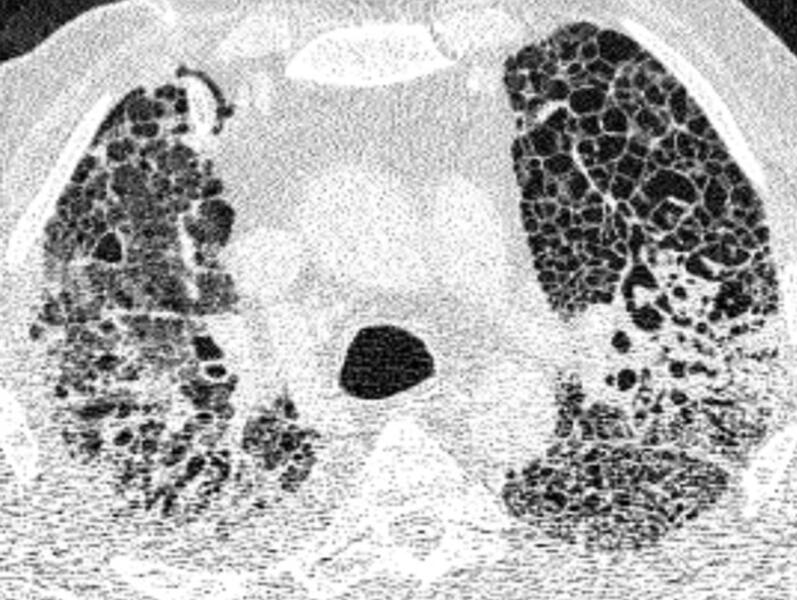

En los pacientes con COVID-19 grave, el daño a los pulmones es tan severo que el cuerpo ya no puede absorber suficiente oxígeno del aire. Los expertos denominan a esta situación "síndrome de dificultad respiratoria aguda" (SDRA).

Los investigadores consideraron una serie de posibles causas de esta insuficiencia pulmonar prolongada, entre ellas un tipo particular de SDRA que provoca una cicatrización pulmonar que da lugar a un engrosamiento y rigidez del tejido. Este tipo de remodelación tisular (conocida como fibrosis) se había observado en algunos pacientes en una fase relativamente temprana de la pandemia.

Este consorcio de investigación interdisciplinar, que reunió a investigadores de toda Alemania, ha confirmado ahora que la insuficiencia pulmonar grave relacionada con el COVID-19 se asocia con frecuencia a una extensa cicatrización de los pulmones.